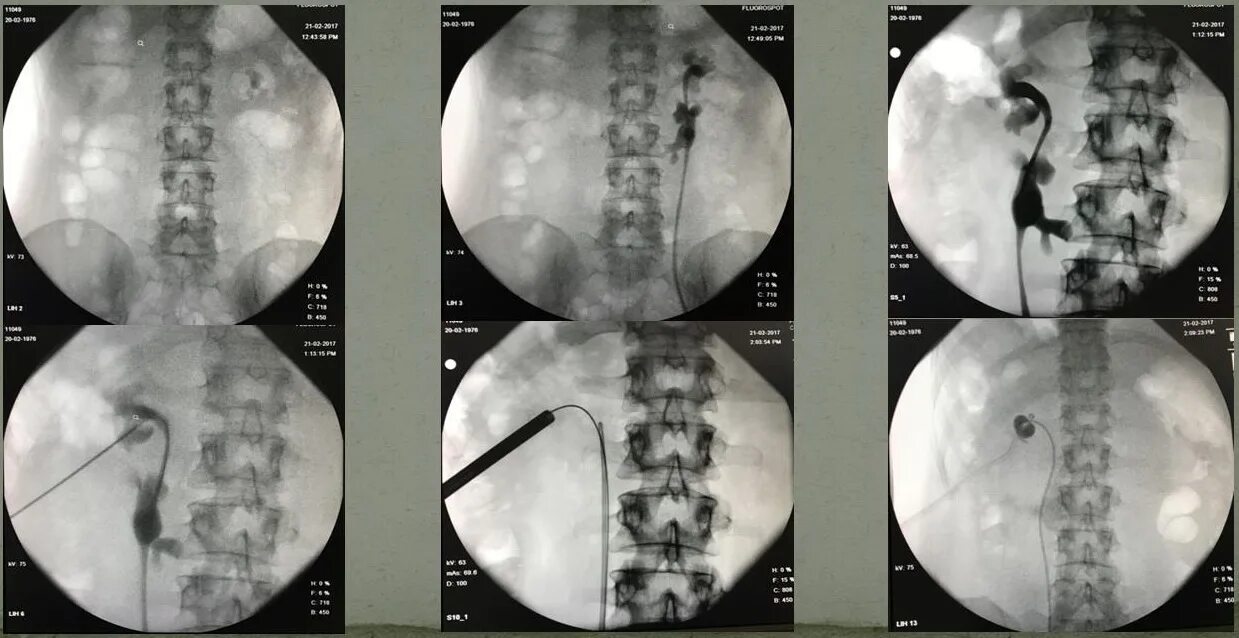

Нефростома в почке что это